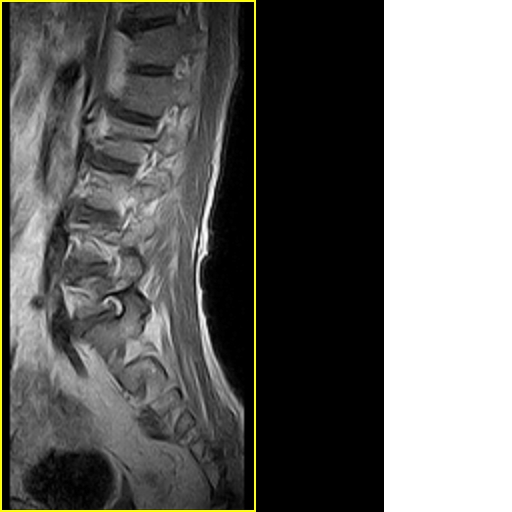

标题: MRI0859:[原创]腰椎,男,78岁,右下肢跛行两月 [打印本页]

标题: MRI0859:[原创]腰椎,男,78岁,右下肢跛行两月

男,78岁,右下肢跛行两月.

退行性骨关节病:增生、椎间盘变性、膨出...

退行性病变:增生、椎间盘变性、膨出[l4-5、l5-s1 椎间盘膨出]

退行性骨关节病:增生、椎间盘变性、膨出..黄韧带肥厚.